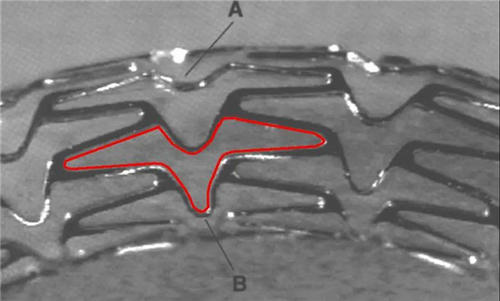

近日一條熱搜引起了人們的熱議,往日的“生命支撐者”心臟支架從很多病患者無法承受的高價降至幾百塊錢,這是因為心臟支架成為首批國家集中帶量采購的耗材品種。心臟支架這么昂貴是因為其體積極小且加工精度極高,如針管般大小的體積進入血管后還能使用球囊將其延展將縮小的血管“撐開”使其技術成本成為了其高昂價格的主要原因,但如今這種讓患者無法負擔之“重”得以減輕也代表著國內的制造技術正在不斷提升。心臟支架作為支撐起生命的器械需要經過嚴苛的測量才能投入到使用當中,心臟支架需要測量的項目有輪廓度、喇叭口、長寬等等,常規的游標卡尺一類通用型工具測量精度不足之余測量效率還十分低,極志高精度影像測量儀成為了心臟支架的設備。

冠脈支架測量

全自動影像測量儀是用于精密工件的測量設備,可以高精度、快速無損地進行心臟支架的各項外形尺寸測量,不觸碰到支架表面就不會在表面留下瑕疵,也符合醫療用品的無污染的要求,滿足醫療設備制造業的對于測量設備的各種需求。二次元測量儀使用三軸精密線性滑軌、精密傳動系統,配備大畫面定位系統,方便快速找到測量位置,具有自動對焦測高的功能,選裝激光后還能進行更詳細的心臟支架外觀測量,功能性、拓展性、穩定性都無可挑剔。極志支持各類測量設備的配置或型號定制,如有測量問題需要解決歡迎致電極志全國服務熱線:020-83515319